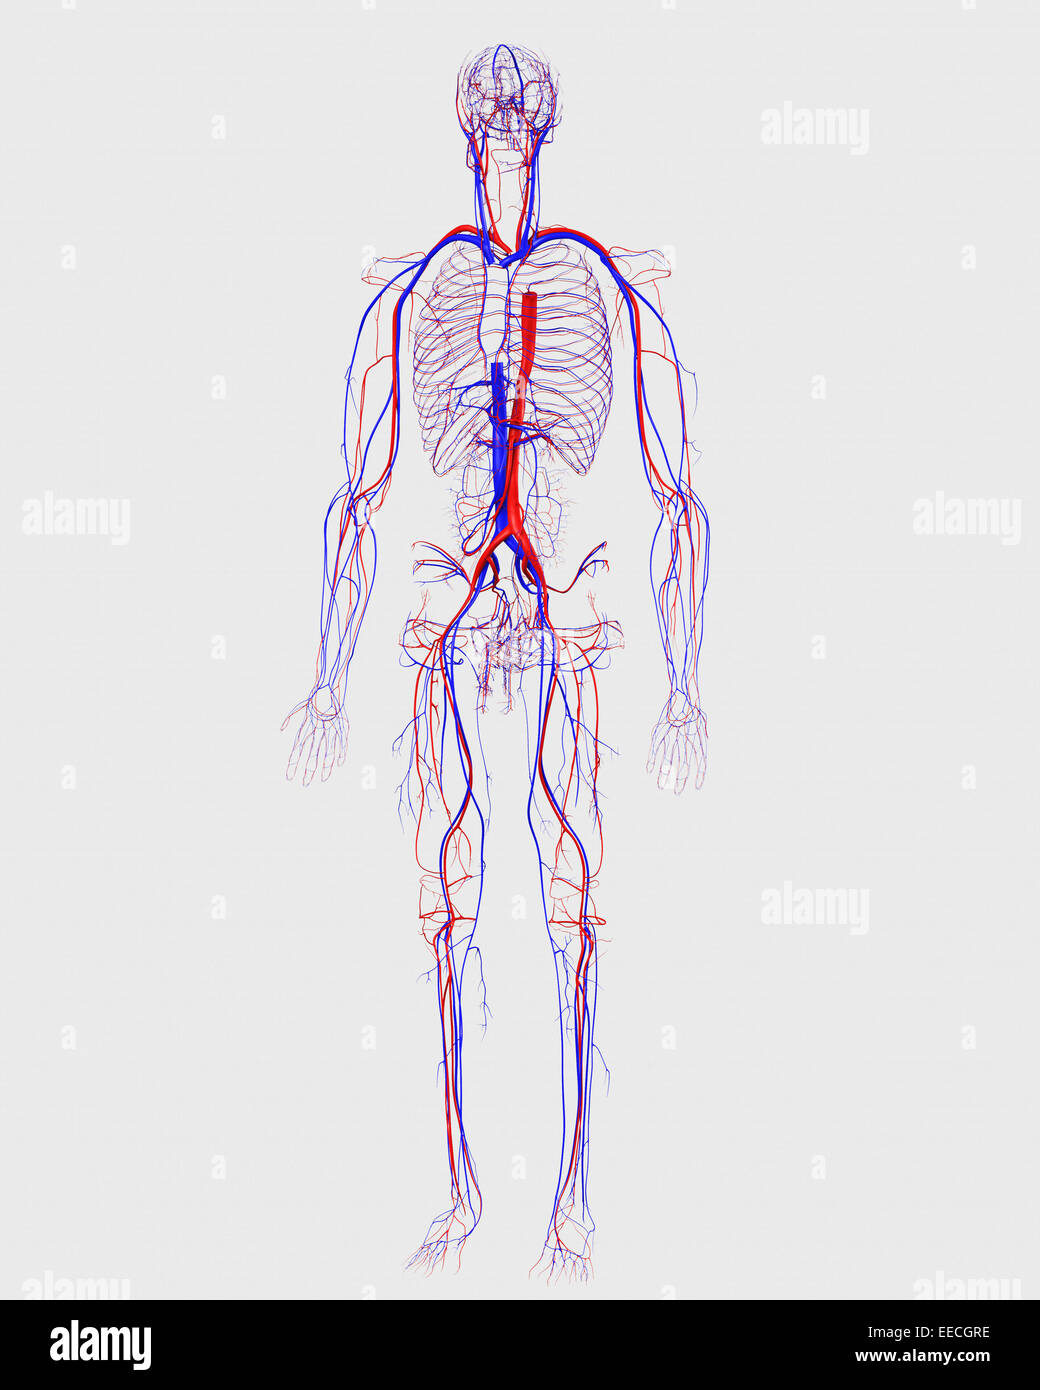

Human circulatory system. Stock Photohttps://www.alamy.com/image-license-details/?v=1https://www.alamy.com/stock-photo-human-circulatory-system-77723282.html

Human circulatory system. Stock Photohttps://www.alamy.com/image-license-details/?v=1https://www.alamy.com/stock-photo-human-circulatory-system-77723282.htmlRFEECGRE–Human circulatory system.